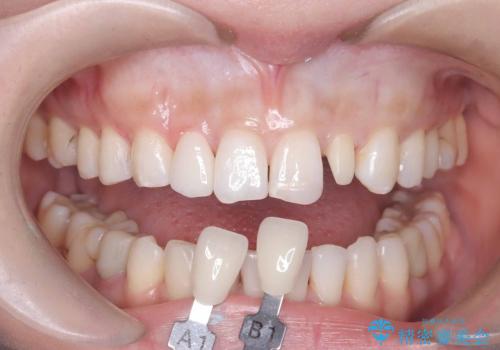

- 歯並びを矯正で整えたあと、上顎左右2番の歯(前歯の横の歯)の「矮小歯(歯が小さい状態)をオールセラミッククラウンで審美修復した症例です。

また、自然な色合いや形になるよう、歯科技工士と連携し、写真を撮影しながら細かく色合わせを行い、周囲の歯になじむよう丁寧に仕上げています。